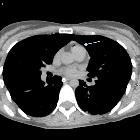

Systemic air

embolism and decompression illnes in a scuba diver.. Gas in pulmonary trunk.

embolism and decompression illnes in a scuba diver.. Arrow shows gas in the inferior vena cava at the confluence of the renal veins.